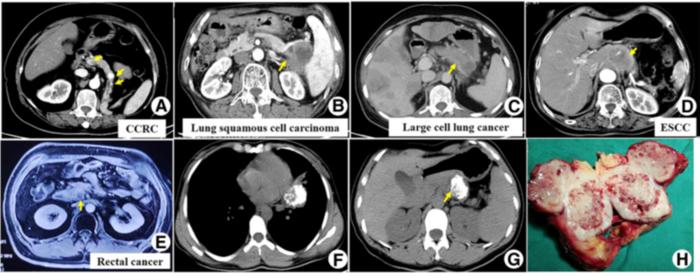

image: Representative CT and MRI images demonstrate pancreatic metastases originating from clear cell renal carcinoma, lung cancer, and other malignancies. Understanding these imaging patterns is essential for improving diagnostic accuracy and avoiding unnecessary or inappropriate treatments. (A) Clear cell renal carcinoma (CCRC). (B) Lung squamous cell carcinoma. (C) Large-cell lung cancer. (D) esophageal squamous cell carcinoma (ESCC). (E) Rectal cancer. (F–H) chondrosarcoma of the mandible.

The research team reviewed 77 patients diagnosed with pancreatic metastases over a 10-year period, between 2013 and 2023. The most common primary cancers were lung cancer (35.1%) and renal cancer (23.4%). CCRC emerged as the most frequent histologic subtype, followed by small-cell lung cancer.